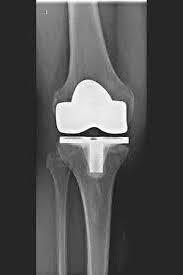

Man spricht bei künstlichen Kniegelenken von Vollprothesen und Teilprothesen. Welche Prothese für Sie in Betracht kommt, Prüfe ich sorgfältig vorher anhand der klinischen Untersuchung, sowie anhand von Röntgenbildern oder MRT-Aufnahmen.

Das künstliche Kniegelenk ersetzt die durch die Arthrose zerstörte Knorpeloberfläche. Der darunterliegende Knochen am Oberschenkel und Schienbeinkopf bleibt erhalten. Manche vergleichen ein modernes künstliches Kniegelenk mit einer

Überkronung bei einem Zahn, der genaue Begriff ist der sogenannte

bikondyläre Oberflächenersatz. Zwischen den neuen Oberflächen am Ober- und Unterschenkel befindet sich das sogenannte Inlay aus einem speziell verhärteten weißen Kunststoff, das im Röntgenbild als Abstand zwischen den Metallteilen zu erkennen ist.